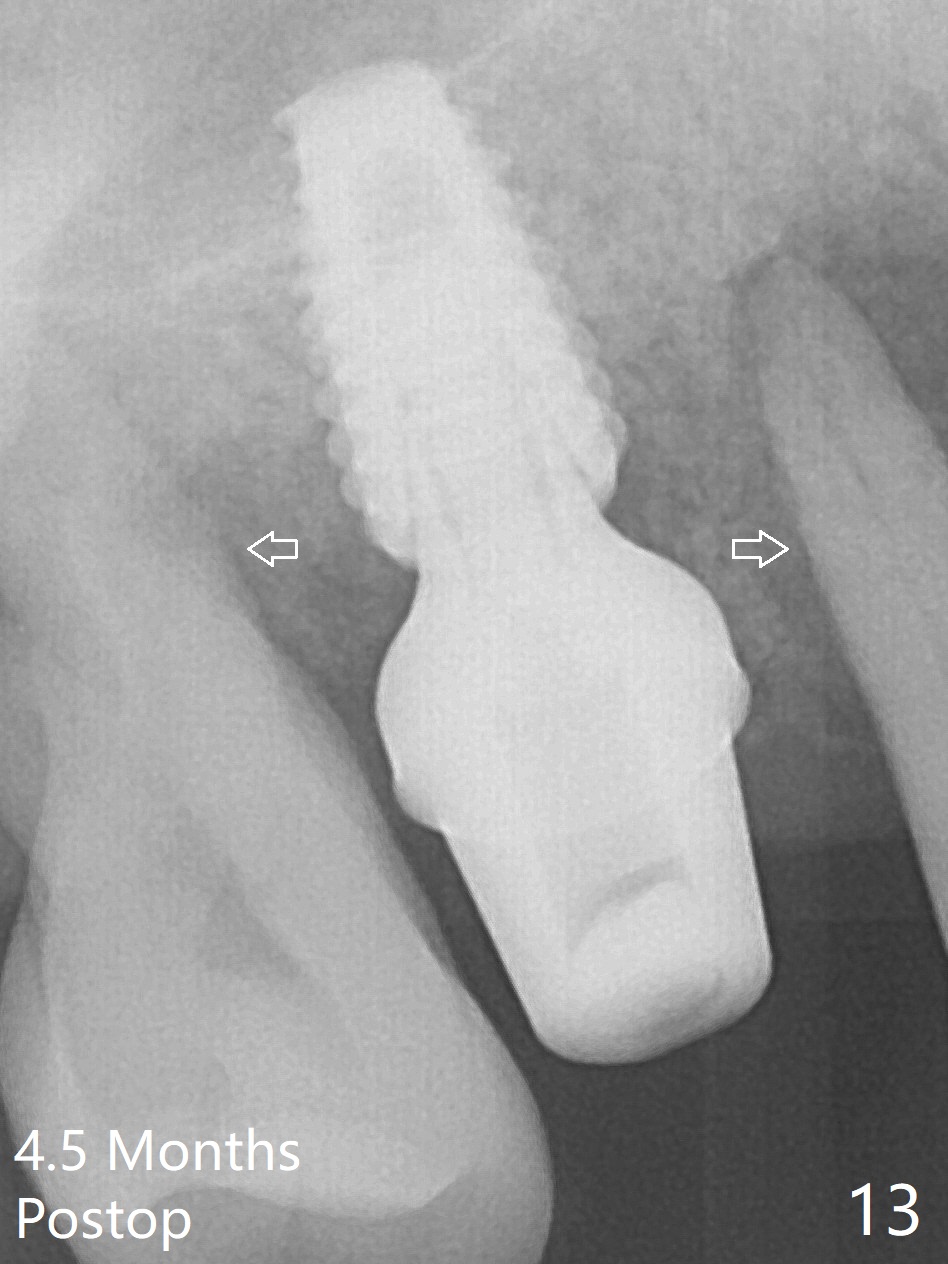

Initial osteotomy depth is 4 mm (Fig.7). The sinus membrane is found to be perforated when the depth increases to 8 mm. The latter could be prevented by taking CT and/or using osteotome. The subsequent osteotomy depth is 5 mm until 4.0 mm in diameter. When the 4.5 mm tap is inserted with initial stability, the shortest implant (8.5 mm, Fig.8 green) will be partially protruded into the sinus and partially exposed in the socket and the cuff of the abutment is expected to be around 6 mm (pink). Since the 5 mm tap achieves primary stability, a 5x8.5 mm implant (following placement of Osteogen plug to repair the perforated sinus membrane) is placed at the level just mentioned (Fig.9). Vanilla Graft mixed with minimal autogenous bone is packed (Fig.10.11 *) before and after insertion of a 6.5x5(4) mm abutment. An immediate provisional as well as a piece of Osteogen plug is fabricated to close the socket gap. The provisional and the abutment are dislodged 1 month postop (Fig.12). The wound has healed. The abutment is reloaded without the provisional. The implant appears to osteointegrate 4.5 months postop (Fig.13); in addition the bone graft seems to have migrated toward the roots of the neighboring teeth (arrows).